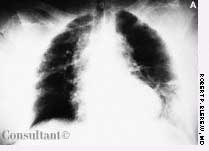

A 97-year-old woman with a history of hypertension and a paraesophageal hiatal hernia presented with abdominal distention and shortness of breath. Three days earlier, she had fallen and sustained a hairline pelvic fracture; she was evaluated in the emergency department and given narcotics for the pain. Subsequently, the patient's abdomen became increasingly distended, and she had no bowel movement for 3 days.